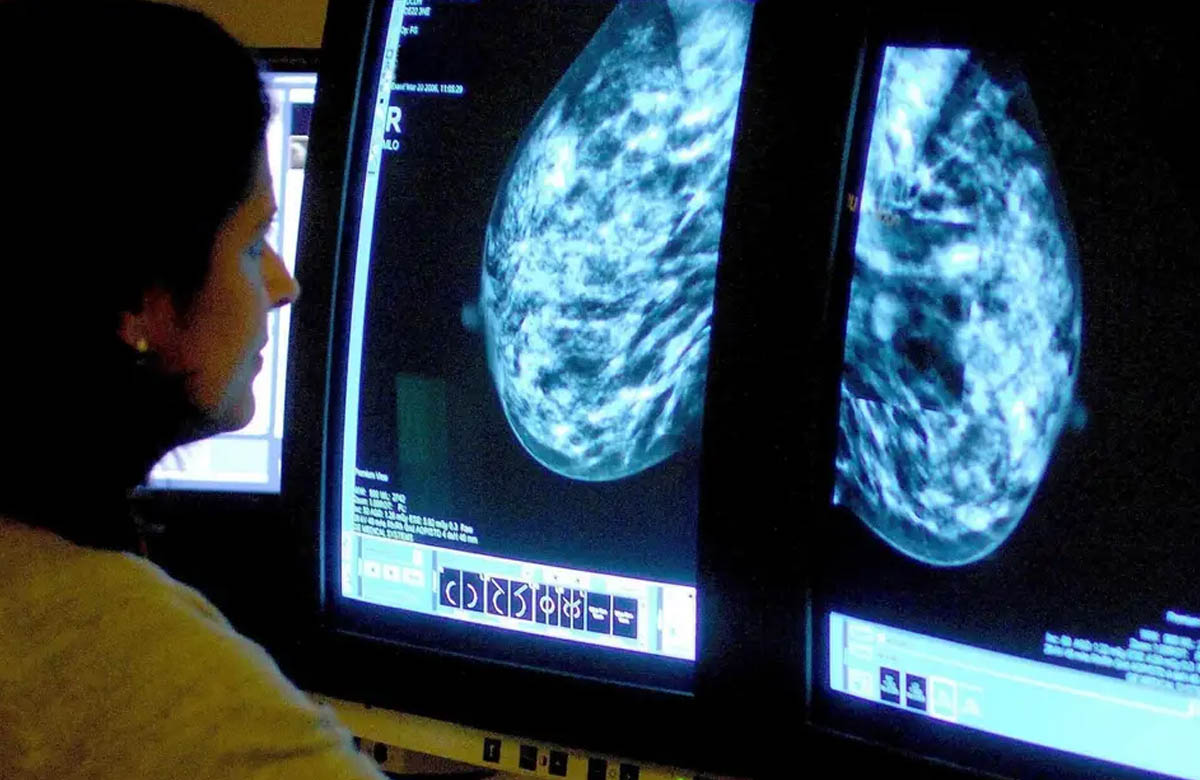

Google Health’de ve İngiltere’de Imperial College London üniversitesinde görevli bilim insanları, yaklaşık 29 bin kadının mamografi görüntülerini inceleyebilen yapay zeka geliştirdi.

Yapay zekanın teşhislerinin tek bir doktorun koyduğu teşhisten daha doğru olduğu tespit edildi.

Tek bir radyolog ile kıyaslandığında yapay zekanın hatalı pozitif teşhis (mamogramın hatalı olarak anormal görülmesi) oranının yüzde 1.2, hatalı negatiflerinin de (kanserin gözden kaçırılması) yüzde 2.7 az olduğu belirtildi.